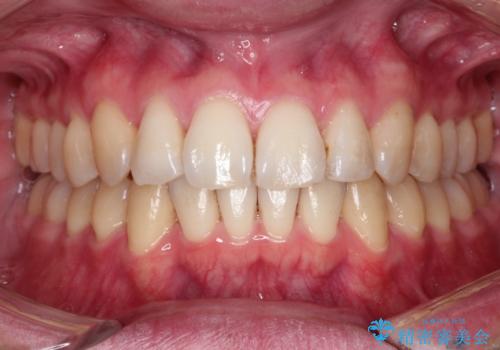

[インビザライン ライト] 短期間(3.5ヶ月)で終わるマウスピース矯正

![[インビザライン ライト] 短期間(3.5ヶ月)で終わるマウスピース矯正の症例 治療後](https://seimitsushinbi.jp/wp/wp-content/uploads/2020/02/2f36cdf472a802b537022ae239b8cb6b-500x350.jpg?v=1580813669)